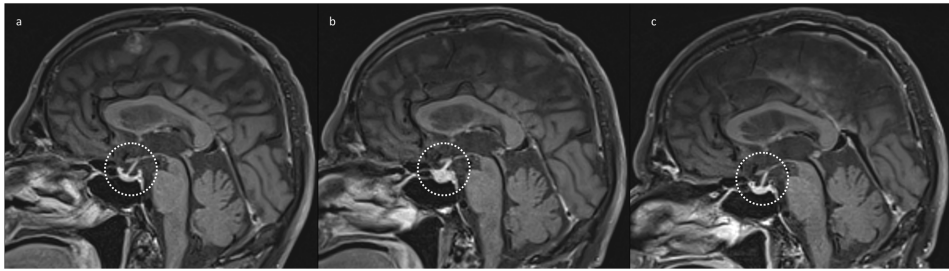

垂体炎是ICIs治疗中最常见的神经影像可见irAE,尤其与CTLA-4抑制剂ipilimumab强相关。典型表现为垂体短暂性轻度增大(通常≤7mm),伴均匀强化和垂体柄光滑增厚。影像演变具有特征性:初期肿胀(治疗后2-3个月达峰),后期萎缩(图1)。需警惕非典型表现如垂体>2cm或鞍区扩展,可能提示转移瘤等其他病变。值得注意的是,约18%患者影像异常早于临床症状,凸显基线影像对比的重要性。